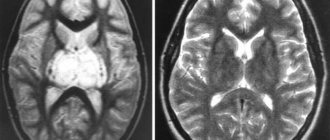

- МРТ или КТ.